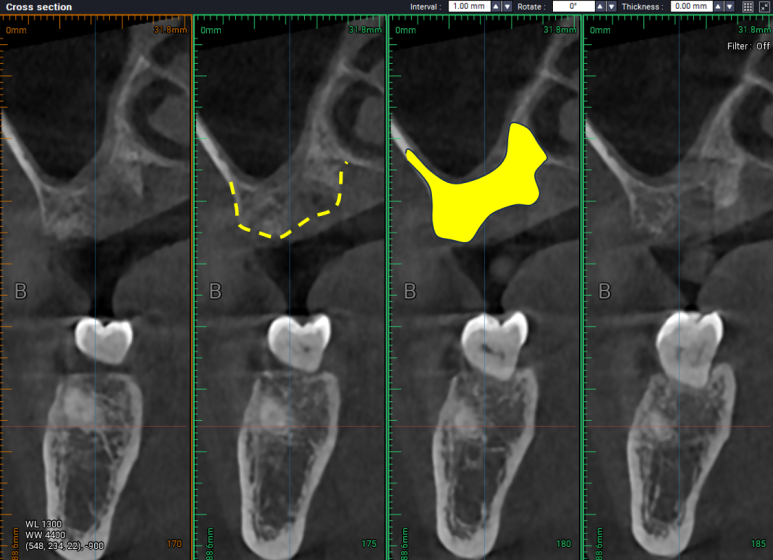

발치&뼈이식술 (치조제보존술) 전과

이를 뽑고 뼈이식을 한 뒤 4개월 쯤 지나서 치과용 CT를 비교해보면,

노란 선은 이를 뽑고 나서 잇몸뼈 하단의 위치, 노란면은 사용 가능한 잇몸뼈의 양.

치아가 있을 때,

염증이 가득해 대부분의 뼈가 없어져서 상악동 하연과 잔존한 치조골 사이의 뼈가 대부분 사라져있는 그 때와 달리,

노란 선은 임플란트를 심을 수 있는 잇몸뼈 상단의 위치, 노란면은 사용 가능한 잇몸뼈의 양.

임플란트를 제거하고 넉넉히 뼈이식을 해둔 결과, 4개월이 지난 시점에서 잇몸뼈가 가득한 듯한 모습!!

치과용 CT 상에서 모의 수술을 시행하였을 때, 임플란트가 위치할 수 있을만큼

잇몸뼈가 넉넉히 재생되었습니다.